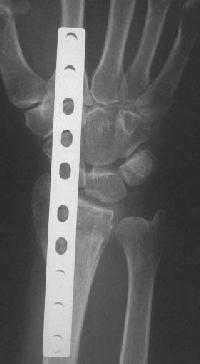

Clinical Example: Distraction plate fixation distal radius fracture

distal radius fracture

distraction plate